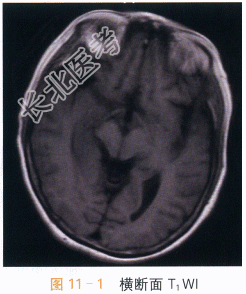

- [材料题] 患者,女,65岁,发热1周,伴神志异常2天。实验室检查:潘氏实验阳性,脑脊液白细胞计数升高,脑脊液蛋白升高。抗巨细胞病毒IgG阳性,抗单细胞病毒1型IgG阳性,抗EB病毒衣壳抗原IgG阳性。影像学资料及分析影像学资料如图11-1~图11-4所示。